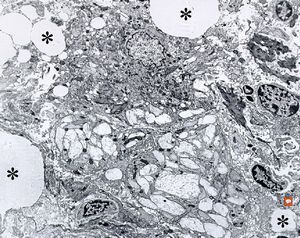

F,58y. | Whipple disease

Whipple disease